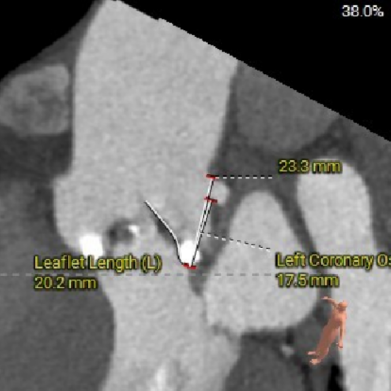

LEFT CORONARY

图片

LCA&LEAFLET

● 左右冠脉开口高度可,左冠切线角度测量瓣叶大于LCA开口下缘到根部距离;

术前考虑右侧股动脉为主入路,左侧为辅助入路。非横位心,主动脉弓角度、宽度尚可,预估输送器过弓难度适宜,跨瓣难度适宜,术中必要时采用Snare辅助。左右冠脉开口高度可,左冠切线角度测量瓣叶大于LCA开口下缘到根部距离,结合瓦氏窦及STJ尺寸预估,冠脉风险适中,建议术中密切关注左冠灌注情况。外周入路走行适宜,腹主中下端和左右髂总散在钙化,血管内径尚可,血管内壁存在不规则纤维增厚和钙化斑,入路穿刺规范操作,小心通过,避免入路血管损伤及相关并发症。重度钙化二叶式病变重度主动脉瓣狭窄,其瓣口面积小,瓣口限制明显,术中瓣膜锚定难度较大,瓣膜植入受二叶瓣瓣叶及团块状钙化挤压存在移位及少量偏多瓣周漏风险,为避免手术并发症,手术预装AV26瓣膜,根据20mm球囊预扩结果选择瓣膜型号,计划瓣膜瓣上3mm开始释放。